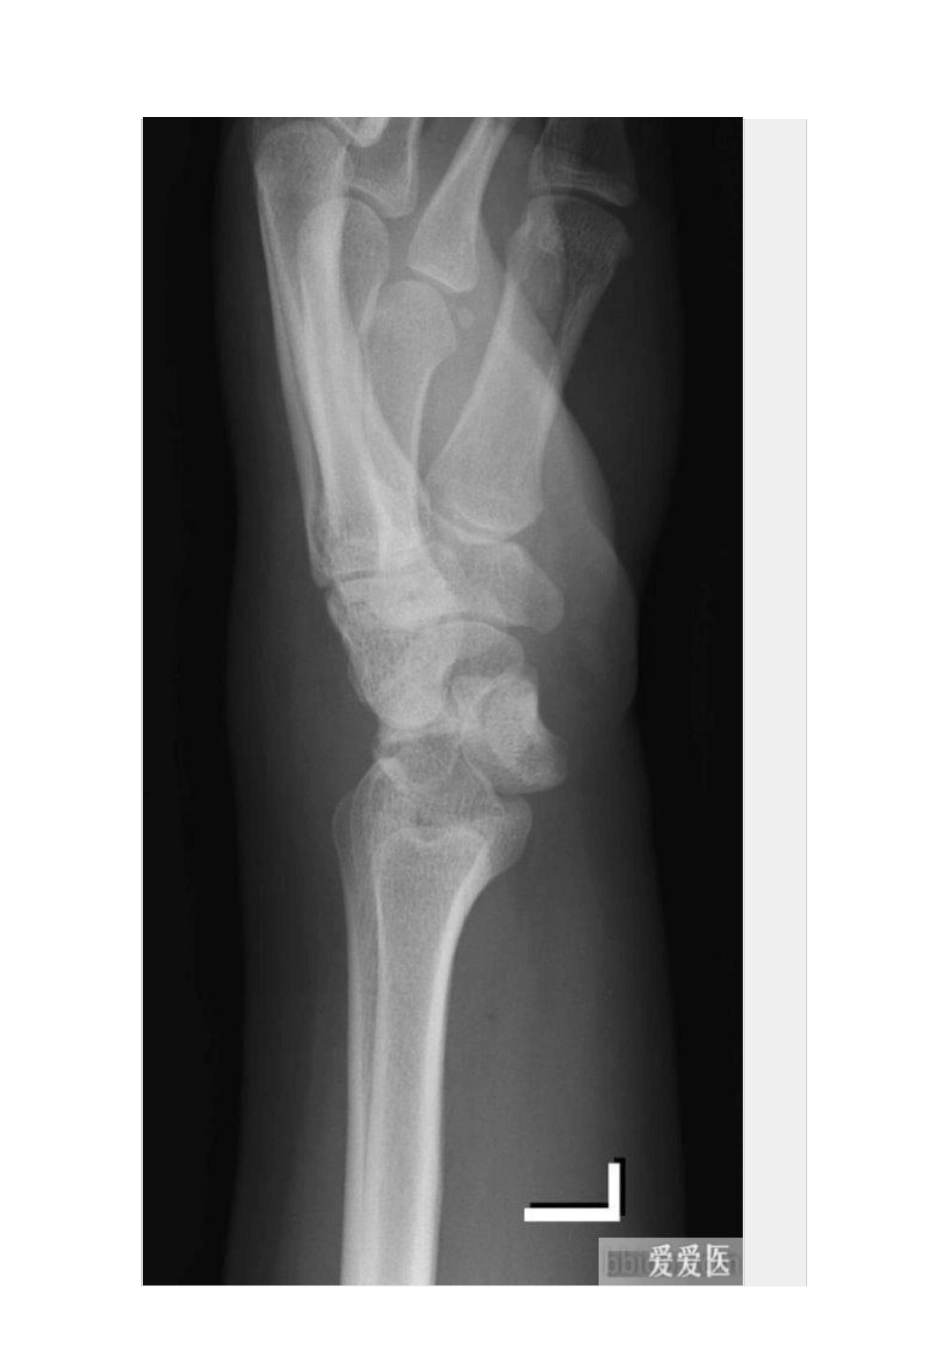

一、月骨脱位受伤机制:手于外撑位跌倒。诊断要点:①正位片月上骨旋转与头骨重叠,头月关节、桡月关节间隙可消失;②侧位片上月骨向掌侧脱位为特征性表现;③舟状骨、头骨与桡骨关系保持原位不变。二、经茎突和舟状骨的月骨脱位受伤机制:手于外撑位跌倒,腕过度背伸。诊断要点:①尺骨或桡骨茎突骨折;②舟状骨中段骨折,近端与头骨重叠;③月骨可向尺侧移位,月骨窝状关节空虚,对向掌侧;④头骨位于月骨后方。三、月骨周围脱位受伤机制:摔倒时手背伸、尺偏和旋前位着地,发生月骨周围脱位。临床表现:腕部肿胀向背侧突出,屈伸活动受限,局部疼痛、压痛。诊断要点:①正位片上头月骨重叠,关节间隙出现消失或变窄;②侧位片上月骨原位不动,桡月关节正常, 月骨上关节面空虚;③头状骨位于月骨背侧缘的后上方;④舟状骨向背侧脱位;⑤可伴有桡骨背缘骨折。四、经舟状骨月骨周围脱位受伤机制:摔倒时手背伸、尺偏和旋前位着地,发生月骨周围脱位。诊断要点:①舟状骨骨折;②正位片上头月关节间隙异常;③侧位片上月骨原位不动,舟状骨近侧骨折块和月骨与桡骨的关系正常,月骨上关节面空虚;④头状骨位于月骨背侧缘的后上方。五、经茎突和舟状骨的月骨周围脱位受伤机制:跌倒时手掌着地,腕过度背伸。诊断要点:①尺、桡骨茎突骨折;②舟状骨中段骨折,近端与头骨重叠;③月骨可向尺侧移位,月骨窝状关节空虚;④头骨位于月骨后方;⑤月骨和舟状骨近端与桡骨关节可正常或向掌侧半脱位。六、三角骨月骨周围脱位受伤机制: 本病的主要表现与月骨周围脱位相似,只是三角骨与钩骨关节间的脱位取代了三角骨与月骨关节间脱位。诊断要点:①月骨、三角骨及桡骨三者关系正常;②其余腕骨向背侧脱位。七、舟状骨脱位受伤机制:舟状骨有旋转性半脱位与全脱位两种类型,两者受伤机制完全不同。前者系中腕关节移位时致舟状骨近端发生旋转性半脱位,较常见;而舟状骨全脱位为直接暴力所致,非常罕见。诊断要点:腕部症状多较严重,有时可伴有神经受压症状。脱出的舟状骨位于皮下,可触及。八、小多角骨脱位受伤机制: 小多角骨脱位较罕见,可为单独脱位,或合并邻近骨的骨折或脱位,脱位的小多角骨多脱向背侧。